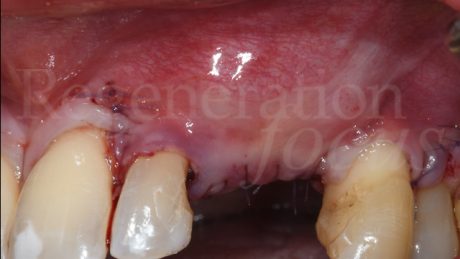

La paziente si presenta per la riabilitazione di una monoedentulia nel II quadrante. Presenta agenesia dell’elemento 24 la cui lacuna è stata colmata dall’elemento 23 distalizzato e pertanto ora si osserva edentulia tra il 22 e il 23 in posizione 24. Si evidenzia clinicamente un deficit bucco palatale di spessore di tessuti molli e recessioni gengivali a carico degli elementi 22 e 23. L’analisi radiografica mostra una quantità di spessore osseo sufficiente per il posizionamento di un impianto di diametro 3.9 mm e 10 mm di altezza.

Si programma una chirurgia plastica volta ad aumentare lo spessore e l’altezza dei tessuti molli della zona edentula. Viene eseguita la tecnica della piattaforma connettivale posizionando un innesto di tessuto connettivale autologo sulla piattaforma occlusale e una matrice in collagene (Geistlich Fibro-Gide®) sull’aspetto vestibolare. La matrice è stata imbibita di Regenfast® e completamente coperta dal lembo spostato coronalmente. A guarigione dei tessuti molli, dopo 6 mesi dalla chirurgia, viene posizionato l’impianto con immediata protesizzazione.

6 mesi dopo l’inserimento implantare è stato posizionato un secondo provvisorio. Protesi eseguita da Dr. Pietro Bellone e Matteo Sangiorgi. Le immagini mostrano la stabilità dei tessuti molli.